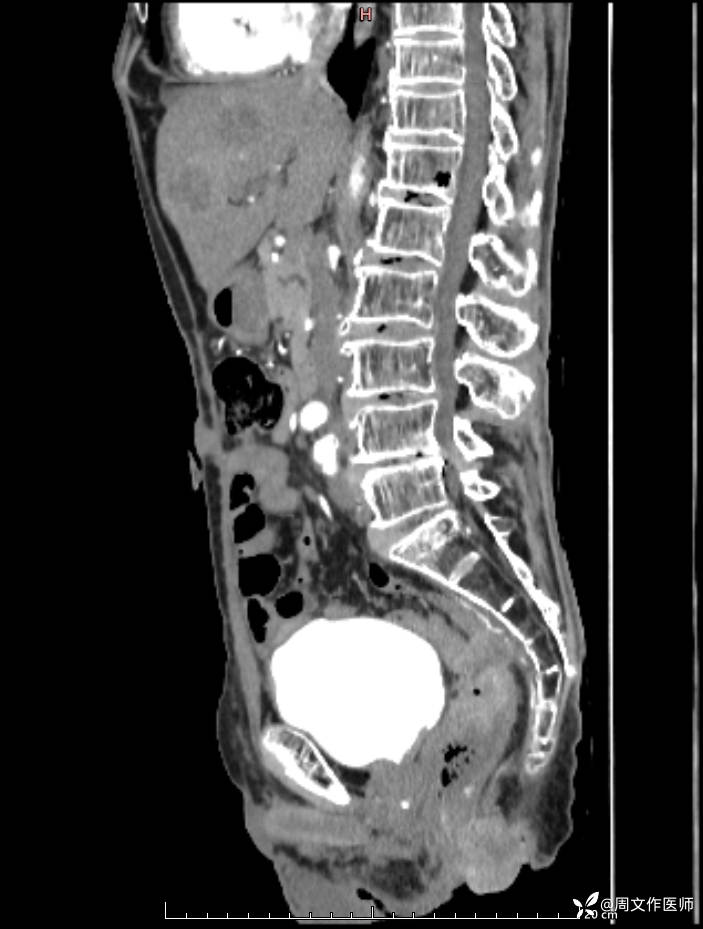

腹部增强CT检查